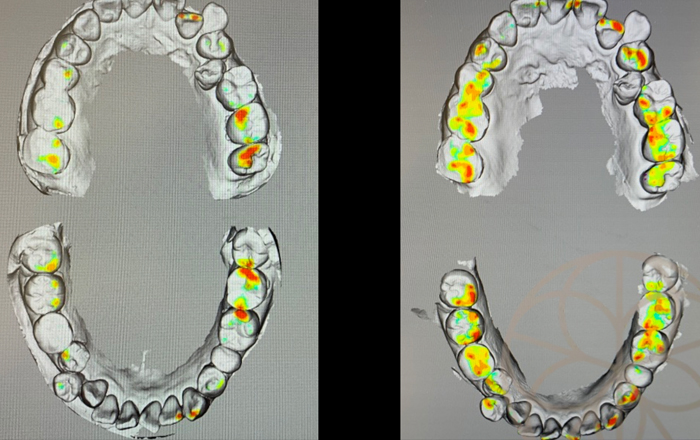

かみ合わせのコンピュータ処理画像

CR(本来のかみ合わせの位置)で多くの歯が当たっておらず、特定の歯のみあたってしまっていることがわかります

咬合調整を行った状態のコンピューター処理画像

左は咬合調整前の咬合接触部位で、右は、ドーソン法にて咬合調整を行った状態のコンピューター処理画像です。

より多くの歯で、まんべんなく当たっていることがわかります。多くの歯で当たっているということは、歯列全体で、力を分散できているということになりますし特定の歯のみ悪くなることを回避できている状態です。また患者様の感覚も以前より、安定してかめるようになった。(以前は咬み合わせても安定していないのでずれる。)肩こり等も楽になった気がするとお伝えいただきました。